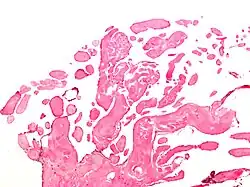

Micrograph of a papillary fibroelastoma, a benign tumor of heart valves. H&E stain.

A subset of the primary tumors of the heart are tumors that are found on the valves of the heart. Tumors that affect the valves of the heart are found in an equal distribution among the four heart valves.[2] The vast majority of these are papillary fibroelastomas. Primary tumors of the valves of the heart are more likely to occur in males. While most primary tumors of the valves of the heart are not malignant, they are more likely to have symptoms related to the valve, including neurologic symptoms and (in a few cases) sudden cardiac death.